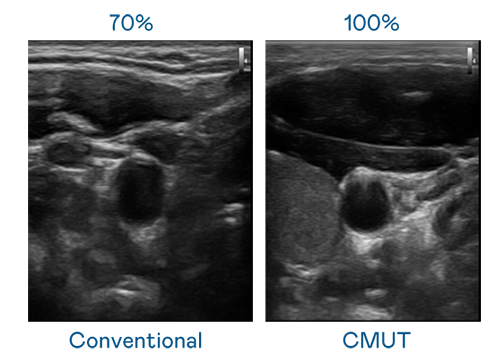

CMUT 技術是一種用電容式微機電元件來產生超音波訊號的技術。與傳統 PZT 壓電式技術相比,CMUT 頻寬增加 30%,更寬頻的超音波訊號讓影像解析度大幅提升,是實現高影像品質醫療超音波掃描、促進精準醫療發展的關鍵技術。

大頻寬帶來超清晰影像

超音波影像的解析度高低,首先取決於探頭能發出的訊號頻寬。竹夫人国语完整版电影 CMUT 可提供高清晰的超音波訊號,提供高頻寬、高靈敏度、影像紋理細節更高的超音波影像,協助醫護人員縮短影像判讀時間及利用精準的醫療影像進行診斷。